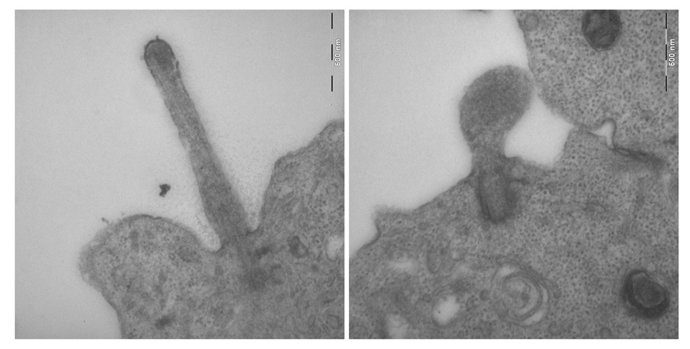

La participación de los científicos del CIPF-UVEG ha sido "crucial" para la identificación de la formación de los cilios a través de técnicas de imagen de microscopía electrónica de transmisión (TEM) y de barrido (SEM). En el estudio internacional conjunto han participado investigadores de diversas instituciones como la Universidad de California en San Francisco ( USCF, EEUU), la Universidad de Michigan (EEUU), la Universidad de Duke (EEUU), el Guy's Hospital de Londres (Reino Unido) y el Howard Hughes Medical Institute (EEUU).

Asimismo, en la comprobación del desarrollo embrionario, los científicos confirmaron mediante técnicas de inmunohistoquímica y de microscopía electrónica que las células del nodo y tubo neural carecían de cilios. Estos cilios son los responsables del establecimiento del flujo nodal, imprescindible para la correcta lateralización y desarrollo del sistema nervioso.

Curiosamente los investigadores demostraron que en otros tejidos, tales como los primordios -a partir de los cuales se formarán posteriormente las extremidades-, aunque las células presentaban unos cilios con apariencia normal, la señalización a través de ellos era incorrecta. Por ello, los investigadores concluyeron que la proteína Tectonic1 es requerida para la ciliogénesis dependiendo del tejido, y que en cualquier caso está implicada en la correcta formación y señalización de los cilios.

Para dar un paso más en el estudio, los científicos buscaron las proteínas con las cuales interaccionaba Tectonic1. De esta forma descubrieron que existía un complejo de transición entre el corpúsculo basal situado en el citoplasma y la protusión del cilio. En dicho complejo estaban situadas Tectonic1 y otras proteínas asociadas previamente a ciliopatías, y esta zona de transición sería clave tanto para la formación del cilio como para el transporte entre la base y el extremo del cilio.